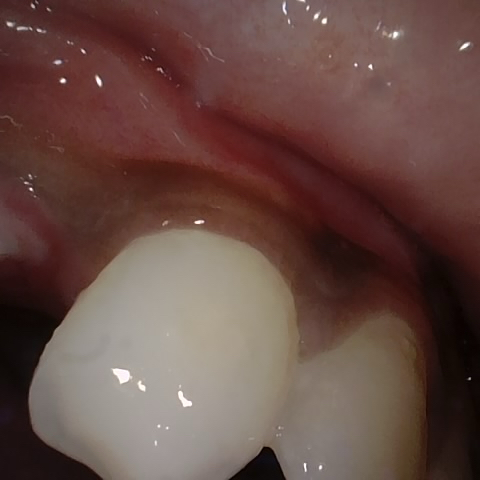

Annotated as "Good"